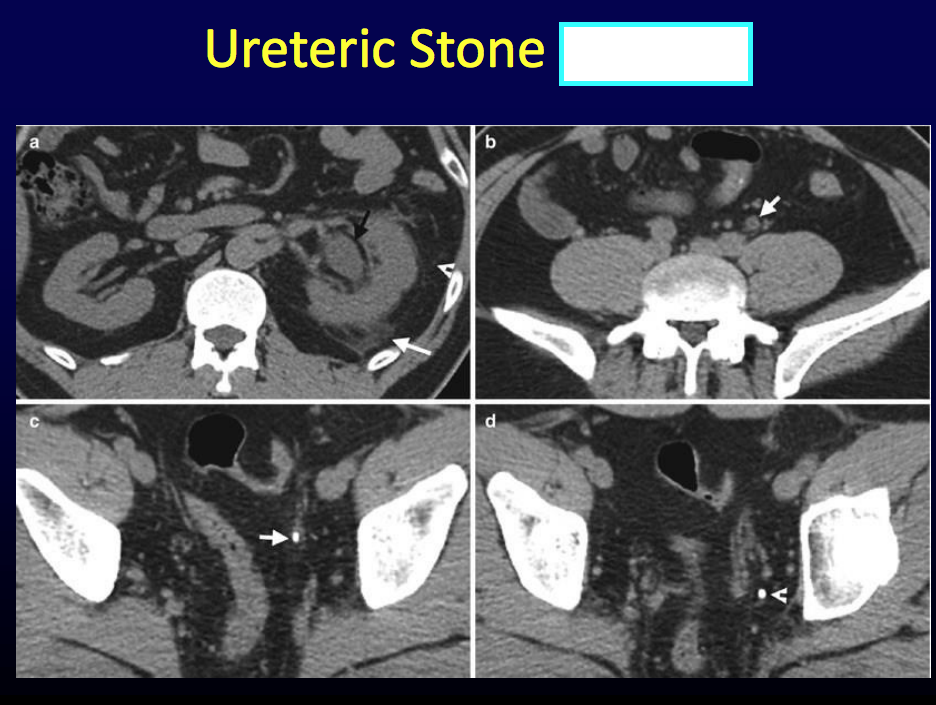

CT fat is [], fluid is [] and bone is [].

CT fat is dark, fluid is grey and bone is white.